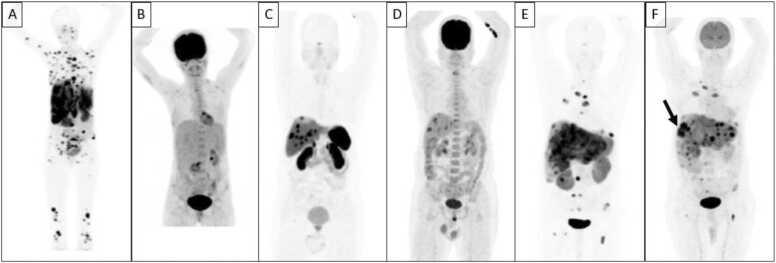

As new molecular tracers are identified to target specific receptors, tissue, and tumor types, opportunities arise for the development of both diagnostic tracers and their therapeutic counterparts, termed "theranostics." While diagnostic tracers utilize positron emitters or gamma-emitting radionuclides, their theranostic counterparts are typically bound to beta and alpha emitters, which can deliver specific and localized radiation to targets with minimal collateral damage to uninvolved surrounding structures. This is an exciting time in molecular imaging and therapy and a step towards personalized and precise medicine in which patients who were either without treatment options or not candidates for other therapies now have expanded options, with tangible data showing improved outcomes. This manuscript explores the current state of theranostics, providing background, treatment specifics, and toxicities, and discusses future potential trends.

随着新的分子示踪剂被确定用于靶向特定受体、组织和肿瘤类型,开发诊断示踪剂及其治疗对应物(即“治疗诊断剂”)的机会应运而生。诊断示踪剂利用正电子发射体或γ发射放射性核素,而它们的治疗诊断对应物通常与β和α发射体结合,这可以将特定的局部辐射传递到靶点,同时对未受影响的周围结构造成最小的附带损伤。这是分子成像和治疗领域令人兴奋的时期,也是迈向个性化精准医学的一步,在这种医学模式下,那些原本没有治疗选择或不适合其他疗法的患者现在有了更多选择,切实的数据表明治疗效果有所改善。本文探讨了治疗诊断学的现状,提供了背景、治疗细节和毒性,并讨论了未来的潜在趋势。